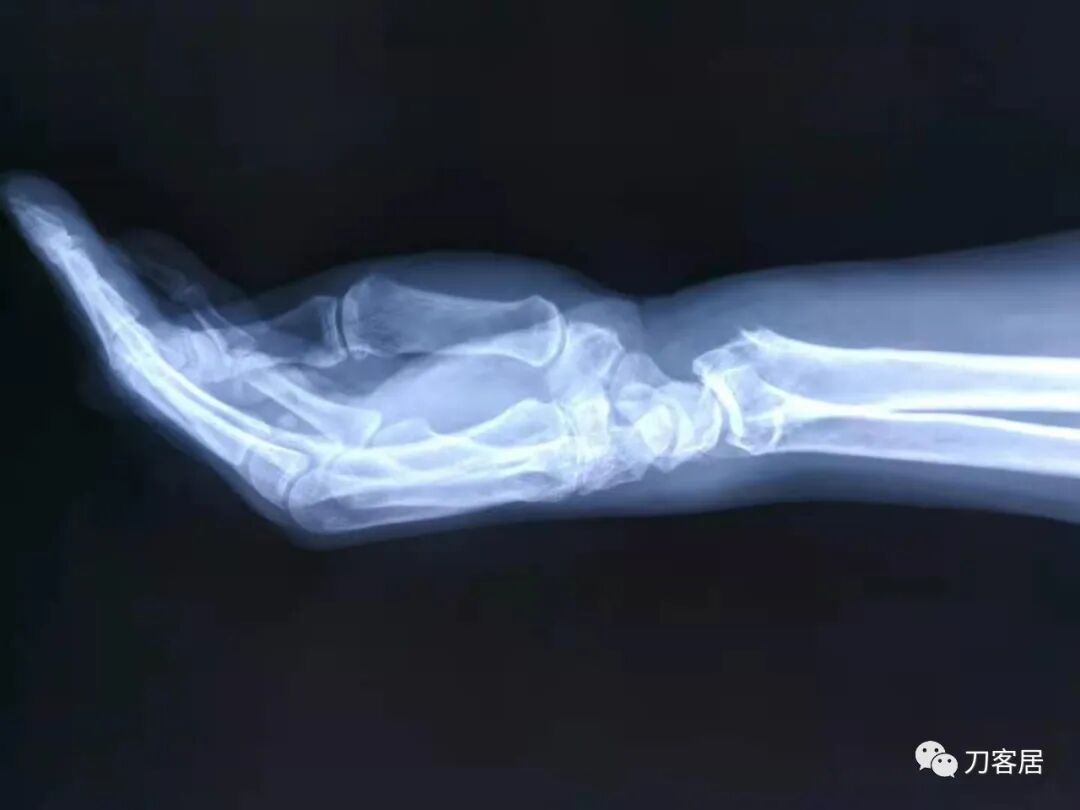

病例2. 没有提供具体患者性别和年龄,为尺桡骨中段双骨折。

图1. 骨折后,复位前。尺桡骨正位片。

图2. 骨折后,复位前,尺桡骨侧位片。

图3. 手法复位后小夹板外固定,尺桡骨侧位片。

图4. 手法复位后,小夹板外固定,尺桡骨正位片。

图5. 骨折愈合后尺桡骨正位片,虽有残余畸形,但功能良好。

图6. 骨愈合后尺桡骨侧位片。功能良好。